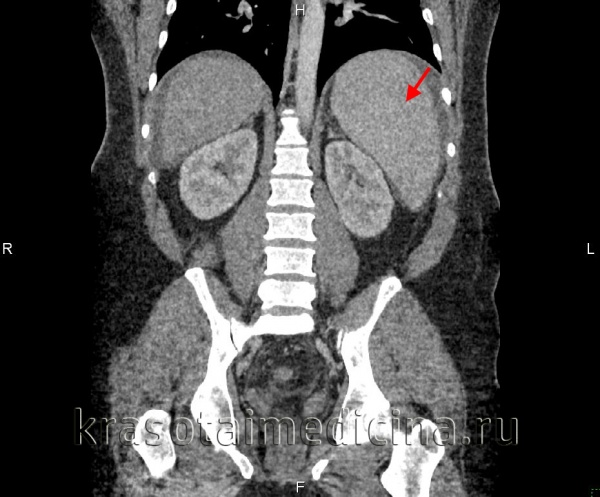

- КТ органов брюшной полости — для выявления опухолей, кист, как на селезенке, так и на других органах

Один из наиболее информативных методов диагностики спленомегалии – УЗИ. Признаками спленомегалии на УЗИ является:

- увеличение размеров селезенки;

- при значительной спленомегалии – смещение соседних органов;

- при заболеваниях самой селезенки, спровоцировавших ее увеличение, наблюдаются ее неоднородная структура, изменения сосудов и так далее.

- компьютерная томография (Т);

- мультисрезовая компьютерная томография (МСКТ);

- магниторезонансная томография (МРТ).